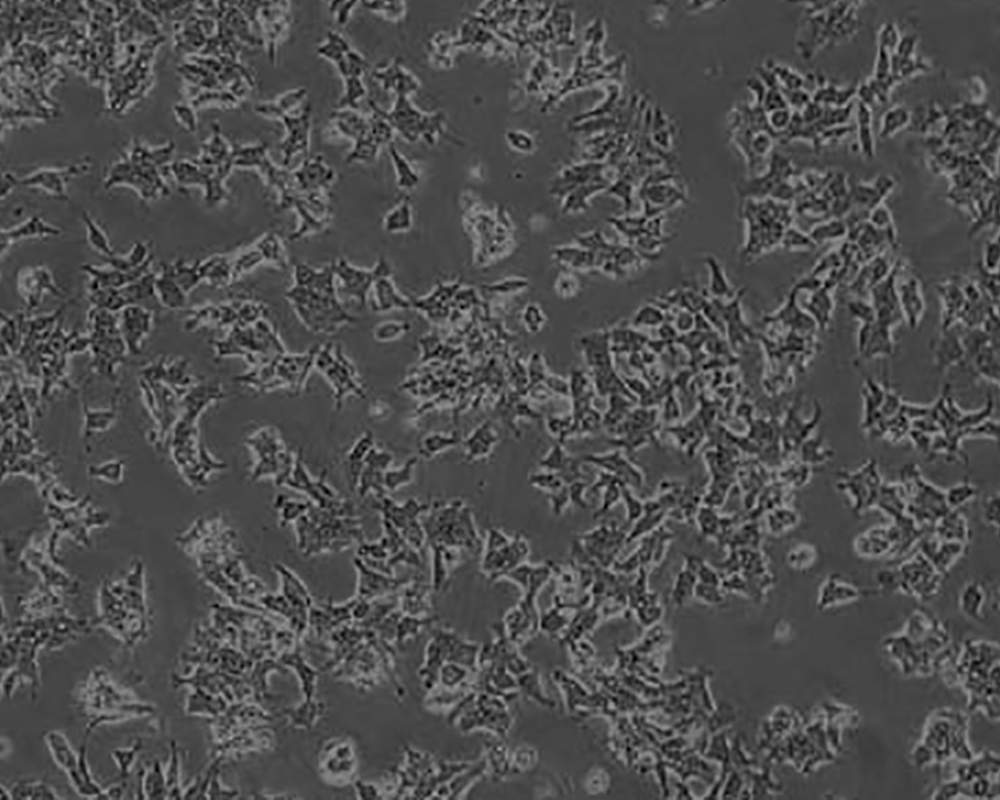

22RV1(22-RV1,22RV1)細胞

產品名稱 22RV1(22-RV1,22RV1)細胞

中文名稱 人前列腺癌細胞

組織來源 前列腺癌;男性

生長特性 adherent

形態特征 epithelial

細胞描述 22RV1是來自異種移植(在閹割引起前列腺癌衰退又在其父親的雄性激素信賴型CWR22嫁接后復發的小鼠中連續傳代)的人前列腺癌上皮細胞系。此細胞系表達前列腺特異抗原。二羥基睪丸脂酮輕微刺激細胞生長,經westernblot檢測溶解產物與抗雄性激素受體抗體起免疫反應。EGF刺激細胞生長,但TGFβ-1不能抑制細胞生長。該細胞在裸鼠中成瘤。